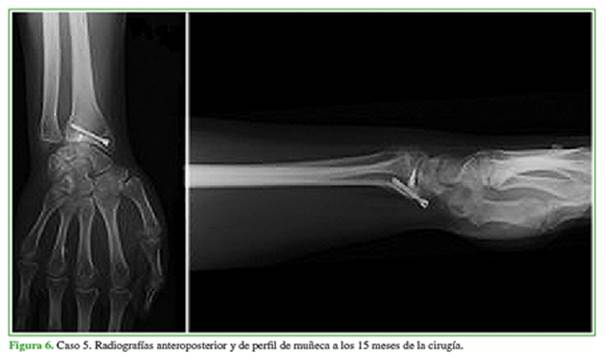

Los controles se realizaron a los 15, 30, 90, 180 y 345 días con radiografías anteroposteriores y de perfil de muñeca (Figuras 5 y 6). Desde el punto de vista objetivo clínico/funcional, se evaluaron los rangos de movilidad en flexión, extensión, pronosupinación y las desviaciones cubital y radial, tomando como parámetro normal de referencia el miembro contralateral sano en una escala del 0% al 100%.

Con un seguimiento promedio de ocho meses (rango 3-12), la evaluación del rango de movilidad de flexión, extensión y pronosupinación y las desviaciones cubital y radial de manera comparativa con el miembro contralateral (Figura 7) (salvo el paciente con lesión bilateral en quien se evaluó cada lesión por separado) determinó que cuatro pacientes tenían un rango de movilidad del 75-99%; cuatro, del 50-74% y uno, del 25-49%, respectivamente. Con los datos recabados de esta manera, podemos establecer que dos pacientes tuvieron resultados excelentes (91-100%); seis, buenos/aceptables (65-90%) y uno, pobre (<65%).